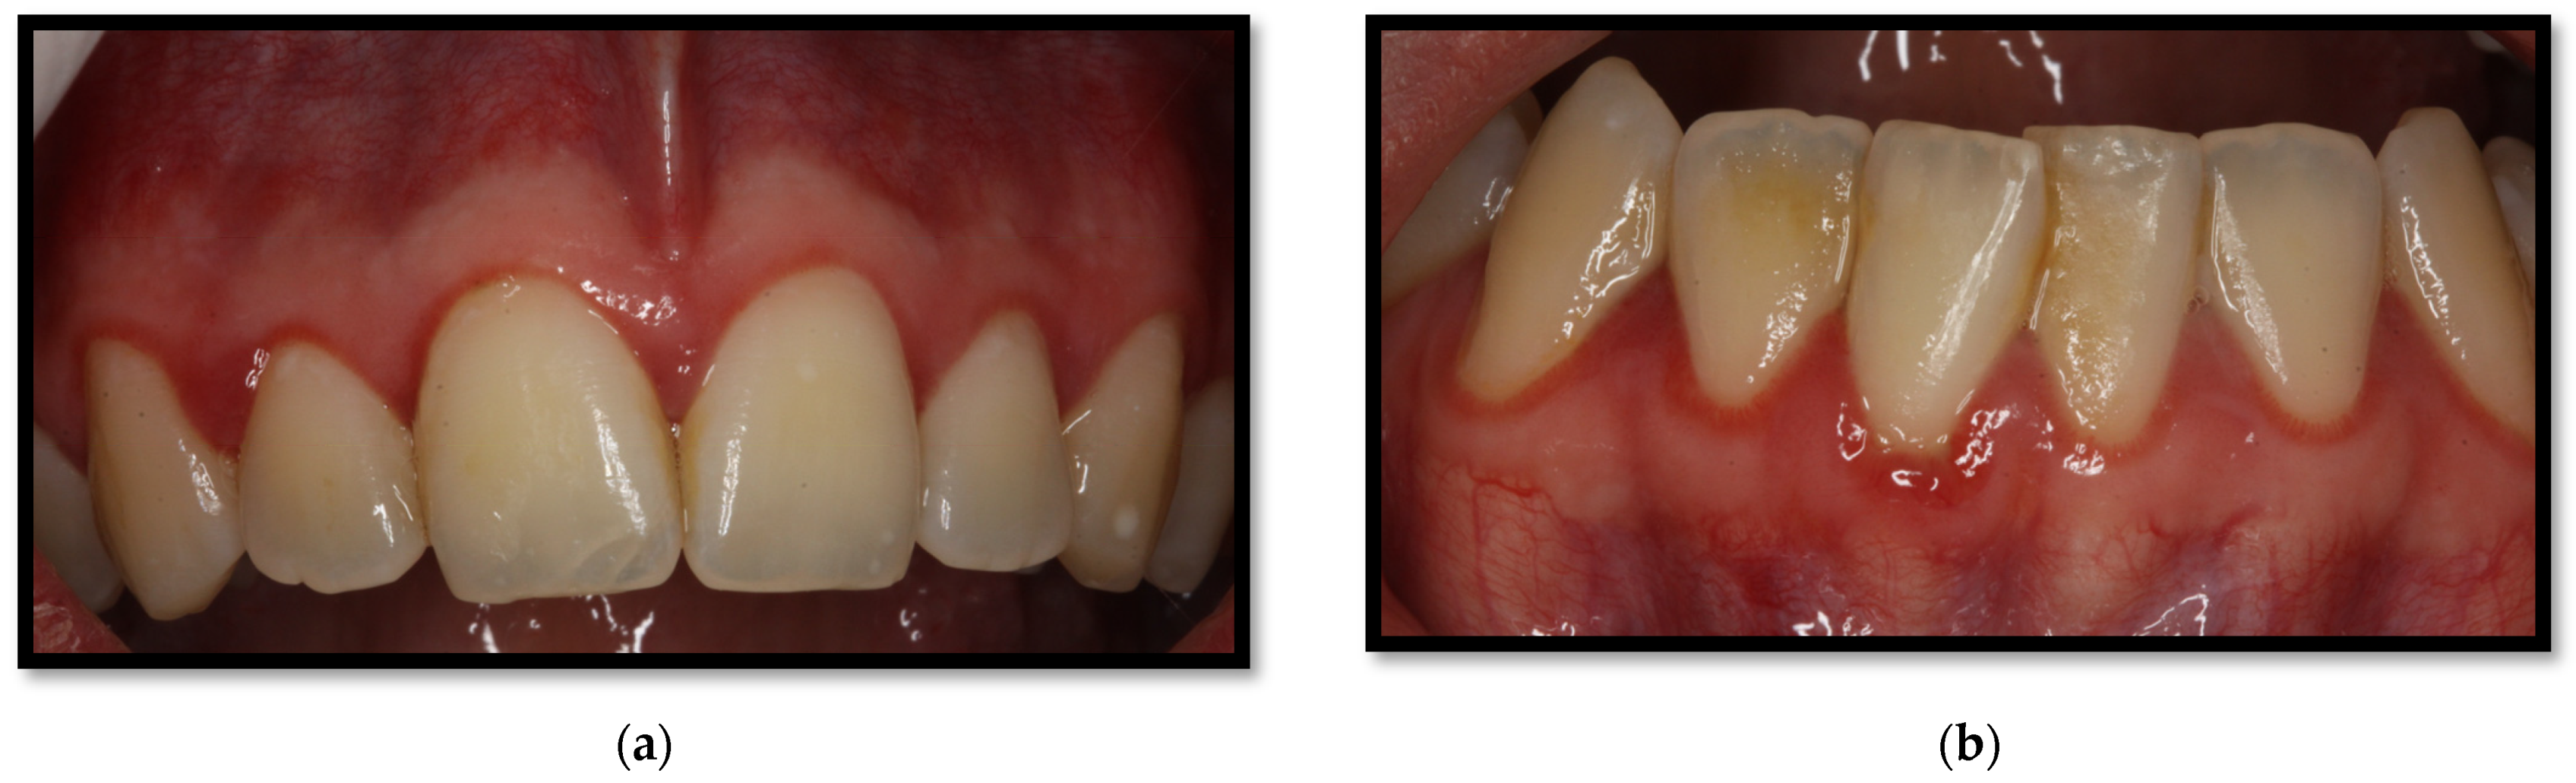

a Preoperative view of gingival recession located at teeth 2126 on

a Preoperative view of gingival recession located at teeth 2126 on Gingivitis Reversal Gingivitis can be reversed with professional treatment and good home oral care, but only if treated early before you have bone loss. Gingivitis is reversible and there's a lot you can do on your own. You can reverse gum disease if you treat it early enough. Periodontitis initially starts with gum inflammation (gingivitis), which is reversible. Steps you can take. Gingivitis Reversal.